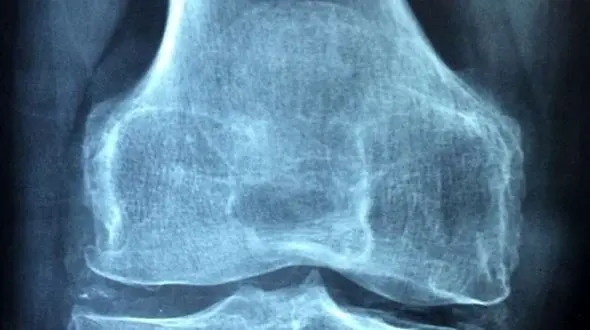

رکنا: رئیس مرکر تحقیقات روماتولوژی کشور با اشاره به آمار ۱۵ درصدی بروز آرتروز در ایرانیان، تاکید کرد: درمان نهایی آرتروز، تعویض مفصل است و درمانهایی تحت عنوان ازن تراپی، تزریق ژل و PRP در مفصل…